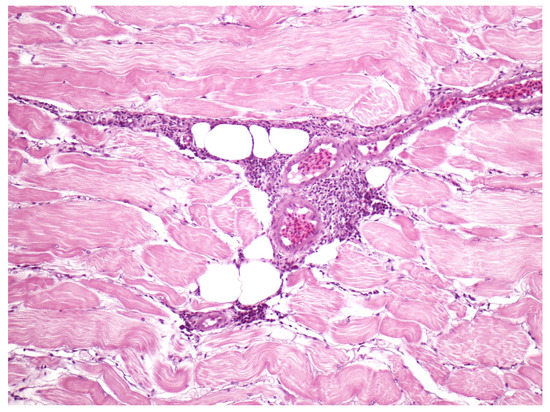

Parasites, granulomas, or both were the most common finding and were most prevalent in the stomach and/or the intestines (Table 1 and Table 2; Figure 2 and Figure 3). Parasitic nematodes were present in the layers of the stomach and attached mesentry of 8 fish (23%), and/or the intestine with attached mesentry in 4/35 fish (11%), and/or the stomach submucosa in 5 fish (14%) (the layer between the lining of the stomach and the muscle layer) (Table 2). Parasites, granulomas, or both were present in control fish and experimental fish from 0 to 38% per group, with no increase with time of out of water (Table 2). In many cases parasites were accompanied by minimal inflammation in the stomach/mesentry and many of the granulomas in the stomach submucosa did not have identifiable parasites (Table 2). There was no damage to the digestive tract, such as perforation of the wall, tissue damage, or infection associated with parasites and inflammation. The number of parasites in sections was small in each fish (up to 5) and inflammation was minimal.

Figure 3. Skeletal muscle perivascular connective tissue moderately expanded by dense aggregates of mixed leukocytes; inflammation with no specific cause identified.